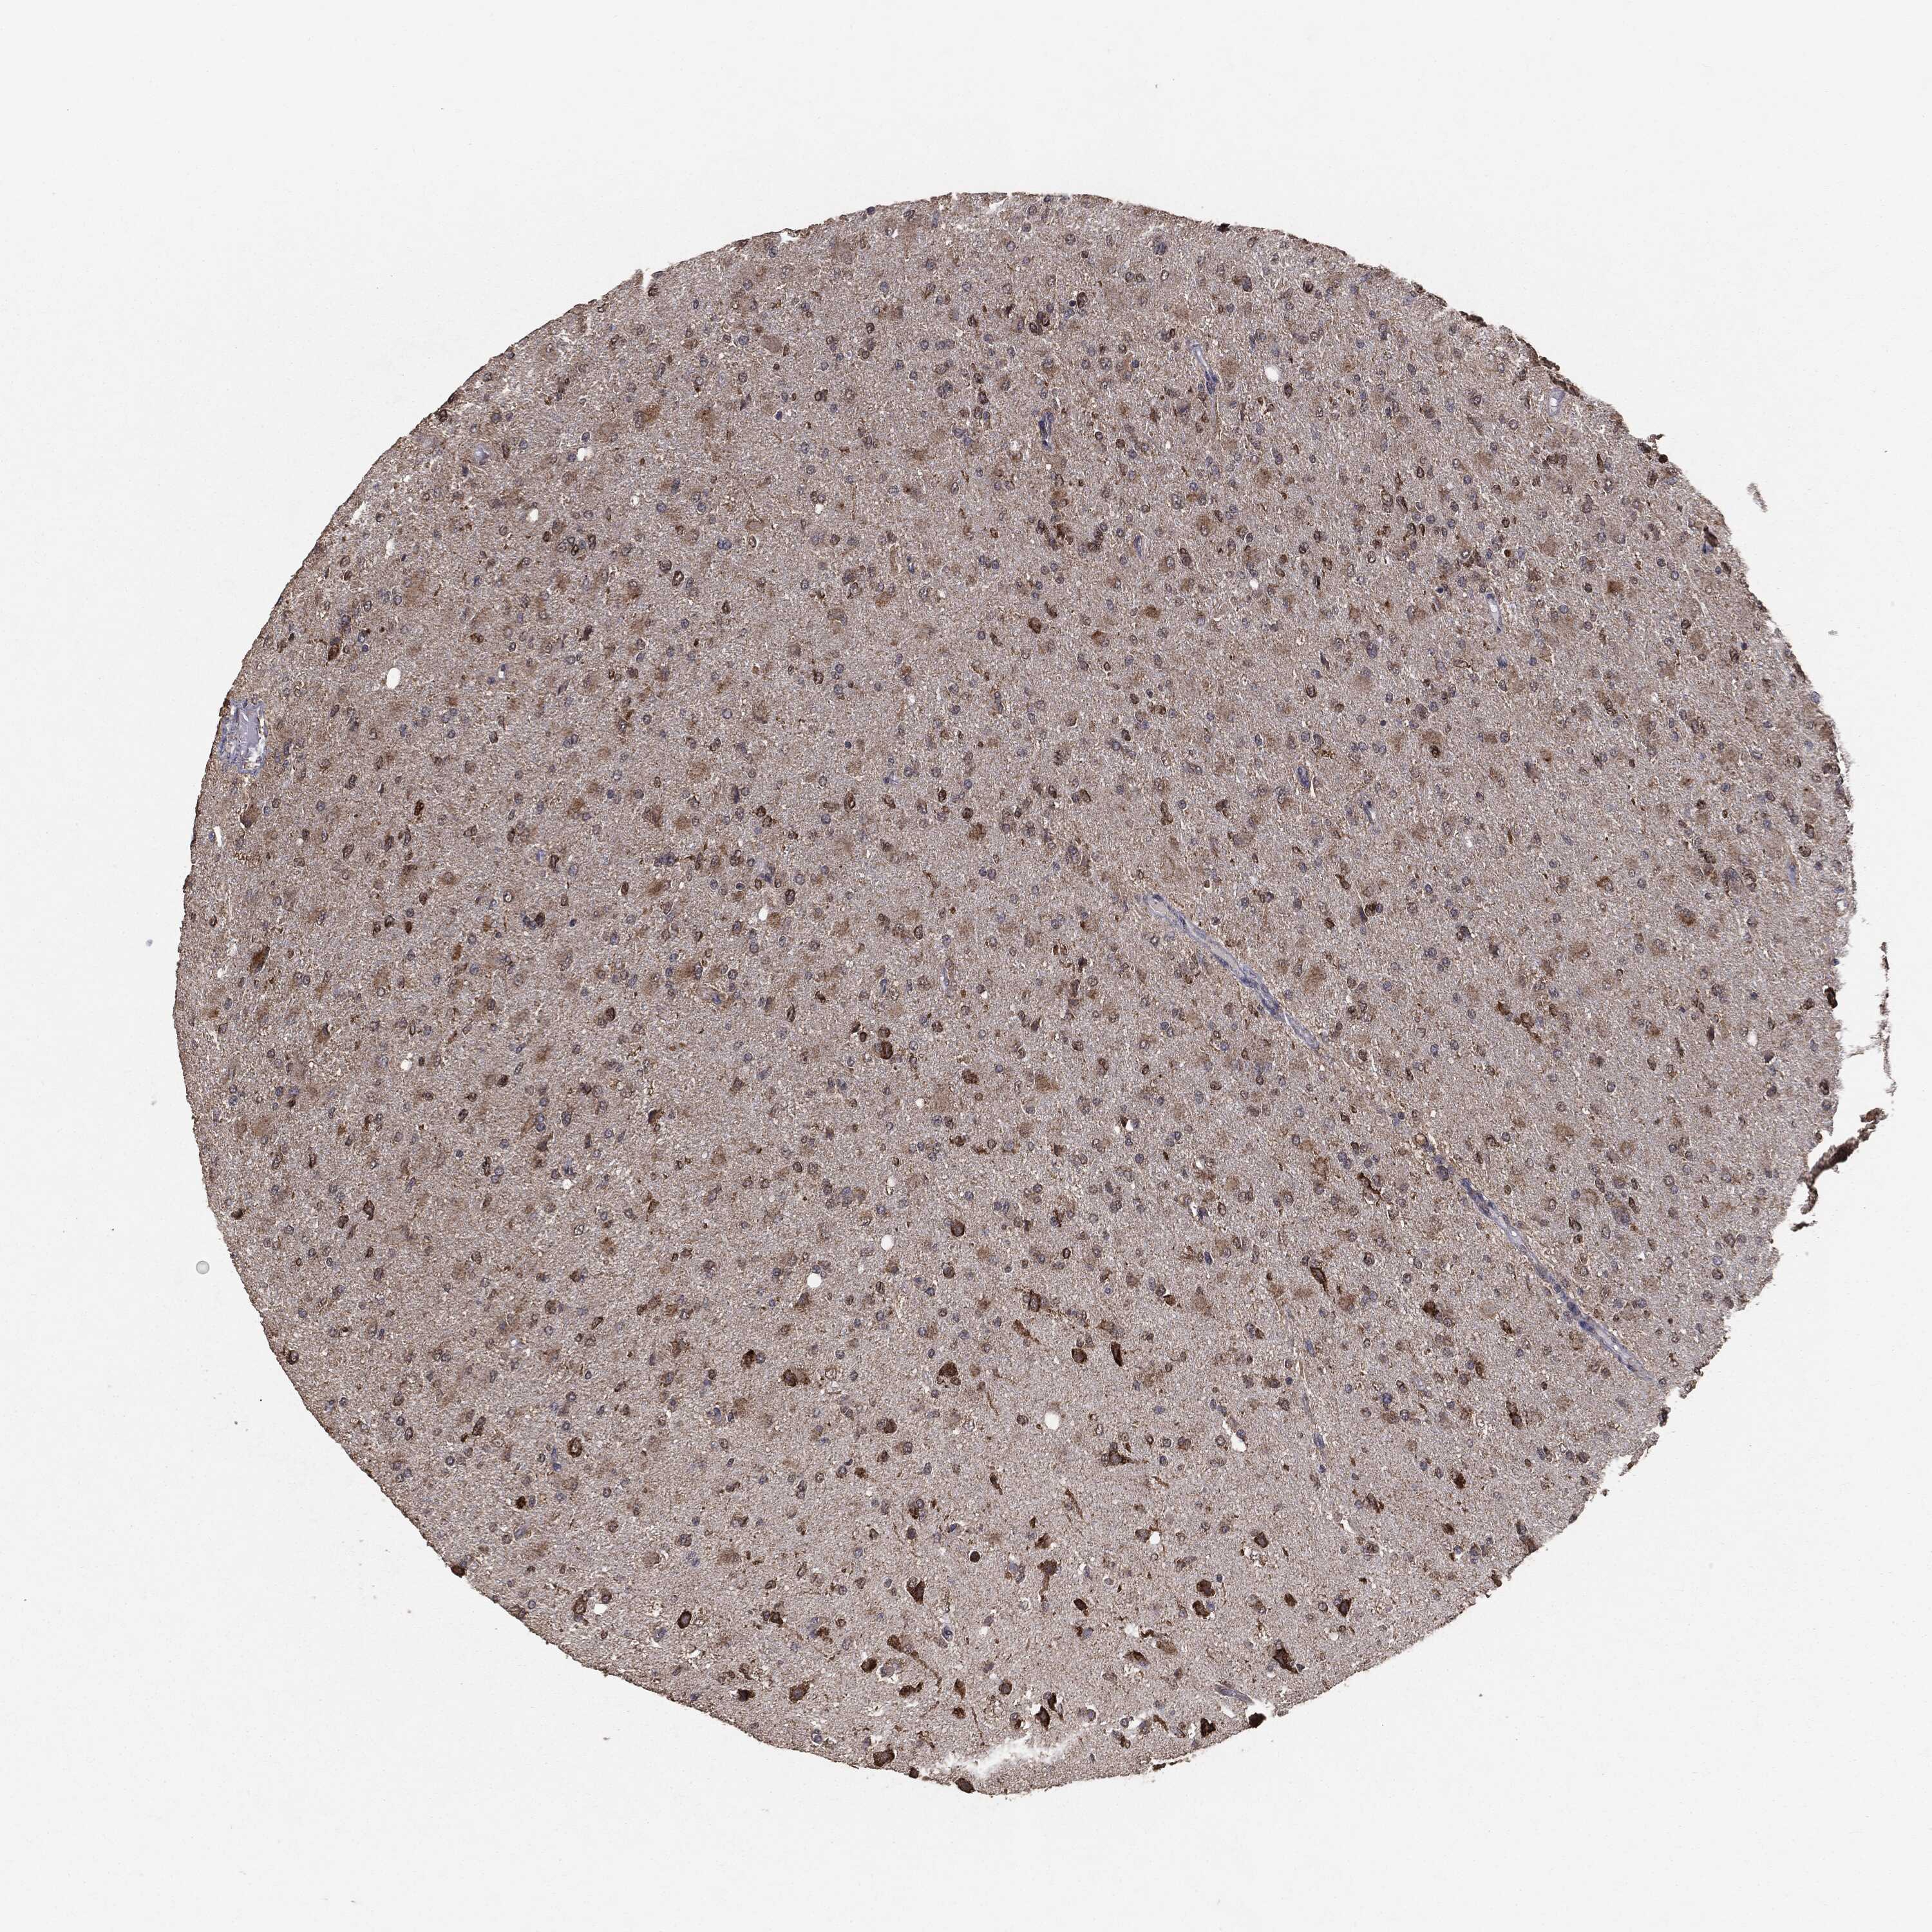

GLIOMA - Protein expressioni

A mouse-over function shows sample information and annotation data. Click on an image to view it in a full screen mode. Samples can be filtered based on level of antibody staining by selecting one or several of the following categories: high, medium, low and not detected. The assay and annotation is described here.

Note that samples used for immunohistochemistry by the Human Protein Atlas do not correspond to samples in the TCGA dataset.

Antibody stainingi

Antibody staining in the annotated cell types in the current human tissue is reported as not detected, low, medium, or high, based on conventional immunohistochemistry profiling in selected tissues. This score is based on the combination of the staining intensity and fraction of stained cells.

Each image is clickable and will lead to virtual microscopy that enables deeper exploration of all samples and also displays staining intensity scores, fraction scores and subcellular localization as well as patient and tissue information for each sample.

CAB069425

CAB080053

CAB080065

CAB080070

CAB080081

CAB080095

CAB080097

Staining

High

Medium

Low

Not detected

Intensity

Strong

Moderate

Weak

Negative

Quantity

>75%

75%-25%

<25%

None

Location

Nuclear

Cytoplasmic/membranous

Cytoplasmic/membranous,nuclear

Glioma, malignant, Low grade

Glioma, malignant, High grade

Glioma, malignant, NOS